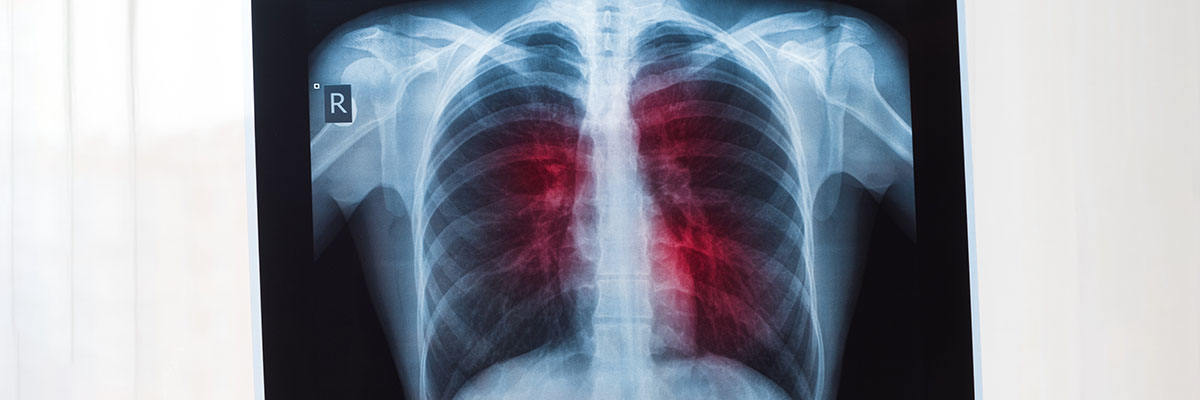

Mahirap i-diagnose ang sakit na kanser sa baga sapagkat ang mga pangunahing sintomas nito ay halos natutulad lamang sa mga sintomas ng iba’t ibang uri ng sakit sa baga. Kailangang sumailalim muna ang pasyente sa ilang laboratory tests gaya ng X-ray, sputum cytology (pagsusuri sa plema), at biopsy (pagsusuri kung may mga cancer cell ang baga) upang masabing ito ay tiyak na lung cancer.